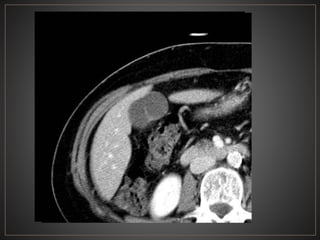

• 48.

CPRE: Dilataciones saculares de CBIH. TC: Simple:Áreas redondas, hipointensas en topografía de CBIH. Contraste: Signo del punteado central. RM: T2: Espacios quísticos hiperdensos